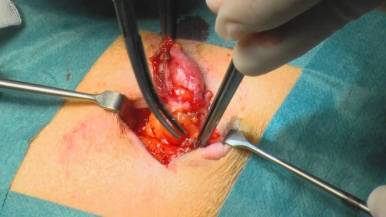

Лечение выпячивания живота проводится путем операции с последующим восстановлением нормальной функции органов. Возможно и консервативное лечение, но пупочные, диафрагмальные и паховые дефекты (с правой стороны или двухсторонние) часто осложняются.

Во время операции хирург создает доступ к пораженному органу, восстанавливает анатомическое положение и ушивает слабые ткани. Операция может проводиться с применением синтетических тканей для полного закрытия дефекта и поддержания органов на своем месте.